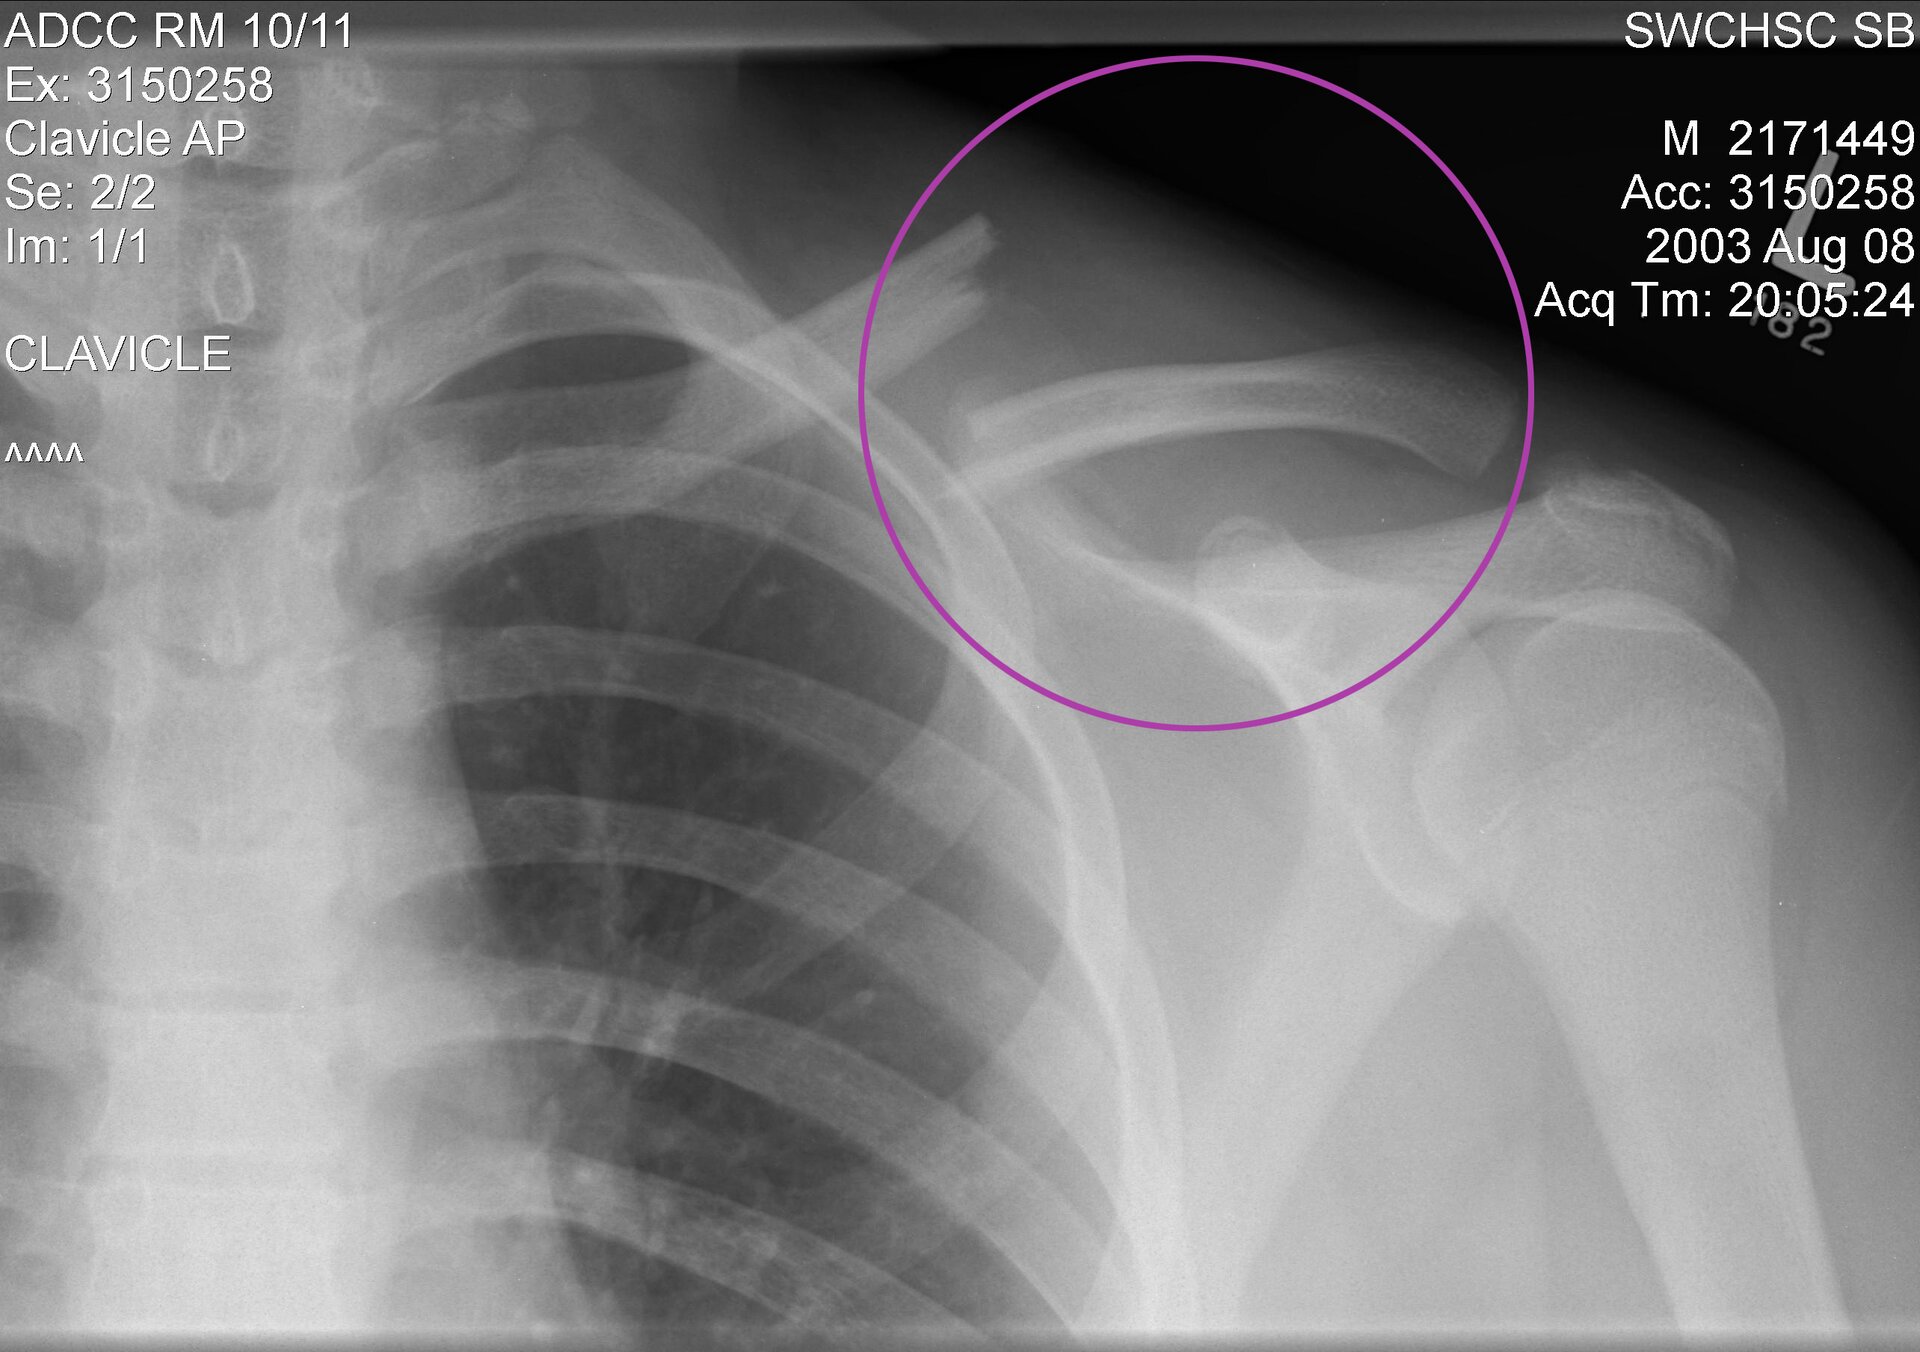

Kości przedstawione na ilustracji to...